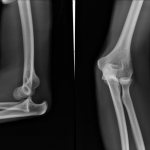

В случае, если вовремя не оказать помощь малышу, будет нарастать отек, что только осложняет дальнейшее лечение. Ведь вправить поврежденную кость будет уже трудно. Родители должны помнить, что заниматься самолечением и самостоятельно вправлять кости при вывихах категорически запрещено – это только навредит ребенку. Без специального исследования – рентгенологического снимка – отличить перелом от вывиха очень сложно.

В случае появления болевых ощущений в районе локтя у ребенка родители должны обратиться в медицинское учреждение, в котором малышу проведут диагностику и окажут первую помощь. Диагностику вывиха у ребенка осуществляют путем пальпации поврежденной области. После этого маленького пациента отправляют на рентгенографию. Благодаря использованию аппаратного обследования определяют степень, а кроме того, локализацию травмы сустава, то есть осуществляют уточнение диагноза. Таким образом, лечение вывиха назначают только после того, как предварительная диагностика подтвердит тщательное обследование.

- Проведение рентгенографии.